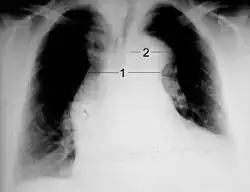

Chest X-ray

Aortic dissection on CXR: Note is made of a wide aortic knob.

Chest radiography may although demonstrate a change in the morphology of the thoracic aorta which can be seen in aortic dissection. Classically, new widening of the mediastinum on radiograph is of moderate sensitivity for detecting an ascending aortic dissection; however, this finding is of low specificity, as many other conditions can cause apparent widening of the mediastinum.

There are several other associated radiographic findings:

• The "calcium sign" describes an apparent separation of the intimal calcification from the outer aortic margin by greater than 10 mm.

• Pleural effusions, more commonly in descending aortic dissections, and typically left-sided.

• Other: the obliteration of the aortic knob, depression of the left mainstem bronchus, loss of the paratracheal stripe, and tracheal deviation.

Importantly, about 12 to 20% of aortic dissections are not detectable by chest radiograph; therefore, a "normal" chest radiograph does not rule out aortic dissection. If there is high clinical suspicion, a more sensitive imaging test (CT angiogram, MR angiography, or transesophageal echo) may be warranted.